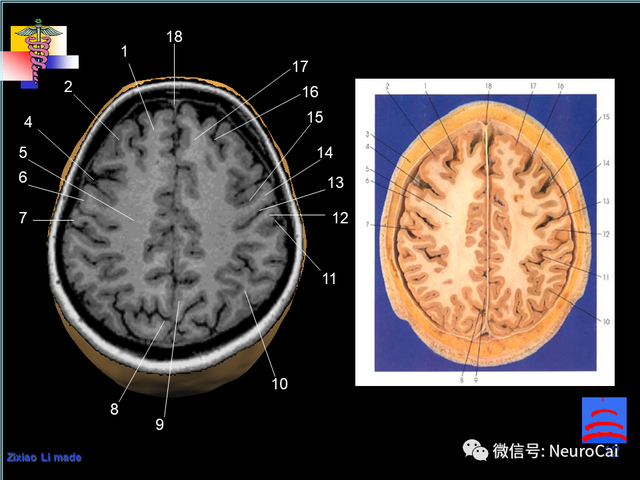

大脑结构图及功能图,人类大脑十大三维解剖图(脑局部解剖与功能图谱)